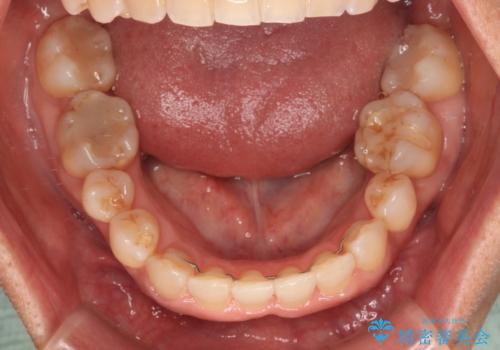

- 骨格的な咬み合わせのズレ、前歯のデコボコとクロスバイトを気にして来院された患者様です。

奥歯の噛みにくさが顕著なためマウスピースではなく、ワイヤー装置による矯正治療を行うこととしました。

下顎の正中を歯1本分ずらした位置とすることで、外見上の骨格的なずれをカバーするように計画しました。